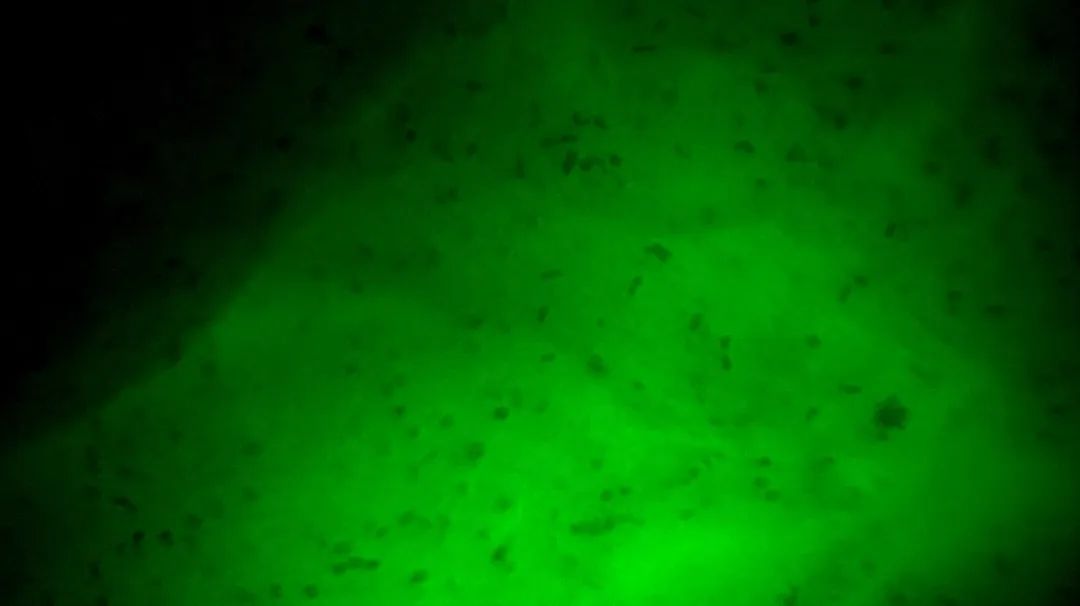

3

陰性,細(xì)胞核形態(tài)正常、分布均勻

本次手術(shù),醫(yī)生在術(shù)中導(dǎo)航及術(shù)中超聲指導(dǎo)下將腫瘤病灶主體切除后,使用EndoSCell?掃查離體腫瘤以觀察陽(yáng)性細(xì)胞形態(tài)作為對(duì)照。隨后使用EndoSCell?在體掃查全瘤腔,在偏后側(cè)緣處發(fā)現(xiàn)了一處細(xì)胞核呈明顯異型、分布密集且不規(guī)則的組織,判斷為殘留病灶并進(jìn)行擴(kuò)切。接著,再次使用EndoSCell?檢查擴(kuò)切處是否切干凈,發(fā)現(xiàn)仍有殘留并進(jìn)行擴(kuò)切。通過(guò)這種逐層掃查、切除的方式,最終在第3次掃查時(shí),圖像顯示整個(gè)瘤腔均為正常細(xì)胞形態(tài),由此判定切緣已達(dá)全部陰性,可進(jìn)入關(guān)顱等后續(xù)步驟。